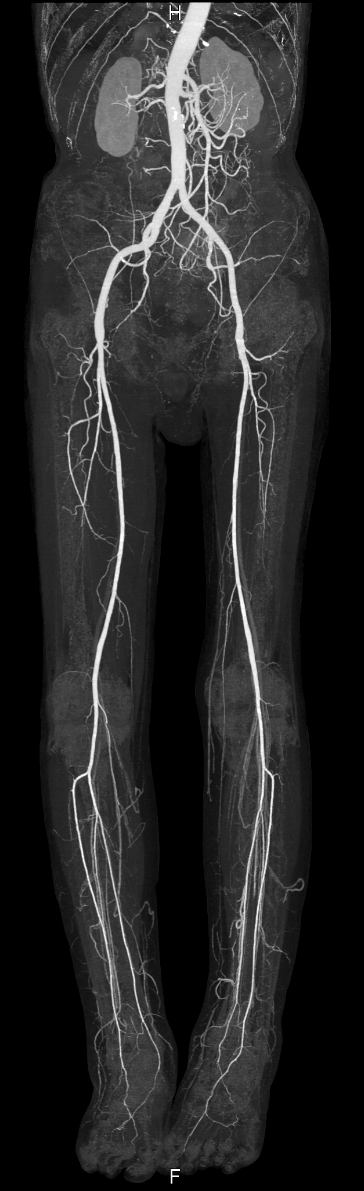

【下肢動脈CT】

足を栄養する血管である下肢動脈の走行や詰まっているところ、狭くなっているところがないかを調べる検査です。

主に下肢閉塞性動脈硬化症の診断や治療方針を決めるのに有用です。

寝台に仰向けで寝た状態で足を固定して造影剤を注入して撮影をします。